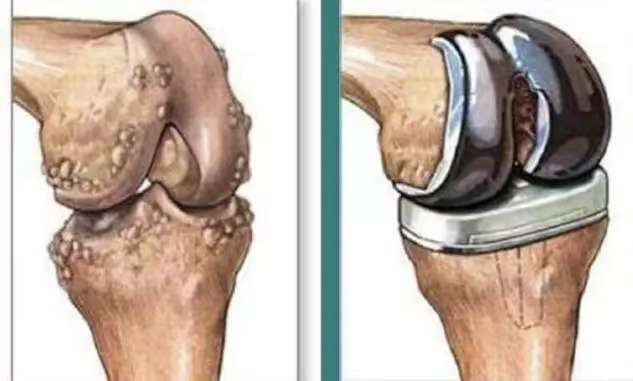

在公园里散步、与孙儿嬉戏、自由上下楼梯……这些看似平凡的日常,对许多深受膝关节疾病困扰的人来说却是一种奢望。当保守治疗无法缓解疼痛,当膝关节变形日益严重,人工膝关节置换手术便成为重启高质量生活的钥匙。 什么是膝关节置换? 膝关节置换手术,是一种将膝关节内受损的软骨及部分软骨下骨切除,并替换为人工设计的假体组件,是一种通过人工关节(采用金属、高分子聚乙烯、陶瓷等材料)置换受损膝关节,以恢复关节功能、减轻疼痛及改善患者的生活质量的治疗方法。 人工膝关节主要包括股骨髁、胫骨垫片、胫骨平台三部分。股骨髁和胫骨平台被固定在股骨和胫骨上,代替被除去的骨损伤部分,通常采用钴铬钼合金、钛合金等,具有极高的耐磨性、良好的生物相容性及机械强度。胫骨垫片附着于胫骨平台上,运动时股骨髁与垫片不断滚动摩擦,垫片承担半月板减少冲击和摩擦的作用。胫骨垫片材质为高分子聚乙烯,具有摩擦系数小、耐磨、抗压、抗氧化等特点。人工膝关节假体的使用寿命通常可以达到15-25年。 什么时候考虑膝关节置换手术? 膝关节是人体最大且最复杂的关节。膝关节的主要结构包括股骨下端、胫骨上端及髌骨关节面。当膝关节出现如晚期膝骨关节炎、类风湿关节炎等问题,引起关节软骨磨损、关节畸形,出现持续的关节疼痛、活动障碍等症状,通过药物、理疗等手段医治无效时,就可以考虑进行人工膝关节置换手术。 术后多久能恢复? 如无特殊情况,膝关节置换术后1-3天即可下床缓慢行走,术后应注意休息、避免剧烈运动,并在医生的指导下进行康复训练,包括膝关节屈伸活动度锻炼、下肢肌力锻炼、踝泵动作等。术后以及康复训练中出现疼痛属于正常现象,3-6月内可逐步恢复。 总而言之,新的膝关节替换原有严重损伤关节后,能够有效解决疼痛和行动不便等困扰。患者日常行动更便捷,提高了生活质量和体验,生活有了更多可能性。但仍需要遵医嘱,在进行康复训练时,务必确保动作轻柔、缓慢,避免过度用力或过度弯曲膝关节,以免引起不适或损伤。如果在训练过程中出现任何不适,应立即停止并咨询医生。 案 例 张女士,60岁,双膝关节疼痛3年余,经过药物治疗和玻璃酸钠关节腔注射后,疼痛症状仍反复,近1月左膝关节症状加重伴活动受限,右膝行走时也时有疼痛。为求系统治疗,前往桂平市中医医院门诊就诊,门诊以“双侧重膝关节骨性关节病”收入院。住院后钟军主治医师询问病史,结合影像学资料并详细查体:左膝关节肿胀、轻度內翻畸形,膝关节内外侧间隙压痛,过曲过伸疼痛,浮髌试验阴性,膝关节活动度0°-90°。 张女士入院后完善了相关检查,以排除手术禁忌症。随后,在骨一科蒋积满团队及手术麻醉室的密切配合下,为其顺利进行了左膝关节表面置换手术。术中,医护人员协同无间,操作精准熟练,在腰硬联合麻醉的辅助下,圆满完成了左膝关节表面置换术。手术过程顺利,手术出血少,术后安全返回病房。 经过手术及术后康复治疗,张女士已能独立行走,彻底摆脱了左膝关节疼痛和活动受限的困扰,生活质量得到显著提高。张女士表示:“没想到手术效果这么好,现在随便走,一点都不痛”!全膝关节置换术,这不仅是骨科技术实力和服务能力取得突破的重要体现,还为辖区患者解除了痛苦,让患者在家门口就能享受到优质的医疗服务,它让无数像张女生这样的患者解除了疾病带来的痛苦,重新拥抱生活的美好。桂平市中医医院骨科将继续致力于医疗技术的创新和发展,为更多患者提供精准、高质量的医疗服务! 健康咨询电话 0775—3395567 门诊地址 桂平市中医医院 急诊楼一楼 骨科门诊 住院部地址 桂平市中医医院 1号楼17楼骨一科 声明:本文仅作医疗知识科普,不作为诊疗方案推荐。具体治疗需经专业医生评估。 |